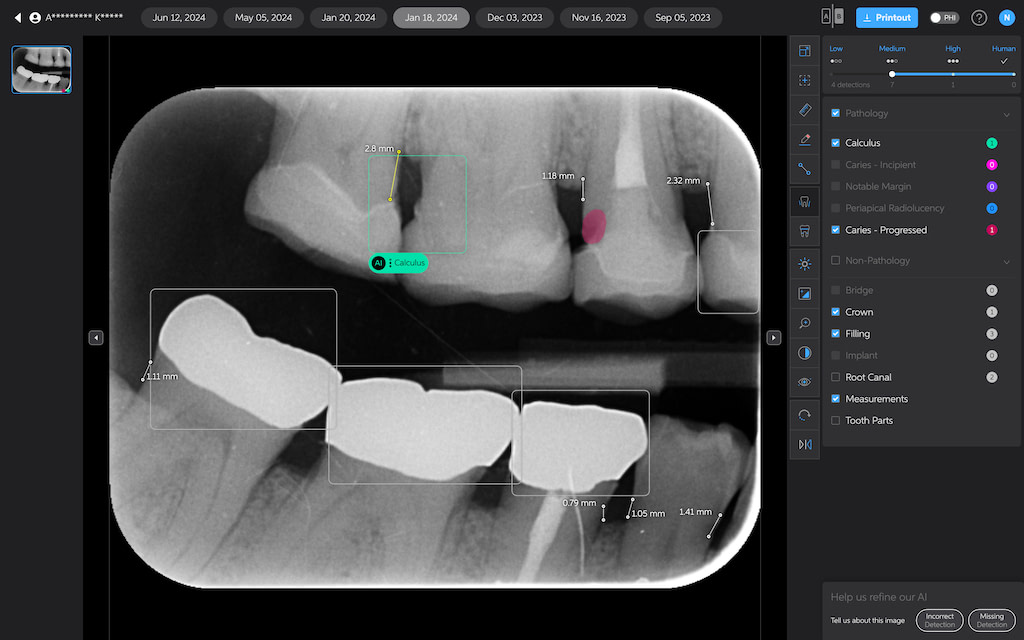

Bone Measurements

The system provides automated measurements from the crest of the bone to the cementoenamel junction (CEJ). These measurements are color-coded to indicate severity:

- White: 0-2.5 mm

- Yellow: 2.5-4 mm

- Amber: >4 mm

This feature is helpful for periodontal assessments, streamlining the process of identifying areas of bone loss. However, it's important to note that image angulation can affect the accuracy of these measurements, a limitation the system acknowledges.

I found these lines to be incredibly useful when describing patients' periodontal health. Cool feature, no doubt.

Calculus Detection

Green squares highlight areas of radiographic calculus. This tool is useful for hygienists and dentists in treatment planning and patient education.

Quite self-explanatory and the system didn't seem to miss often, if ever.

Caries Detection

The best for last and arguably the most well-thought-out feature. Especially with the tooth segmentation mode, which makes it easier for patients to understand their diagnosis and treatment plans.

The system uses two shades of pink to indicate potential caries:

- Light pink: Incipient caries (100% in enamel) - we will often review

- Darker magenta: Caries extending into dentin - we need to restore

The system even provides a percentage breakdown of enamel vs. dentin involvement. I have been blown away by its accuracy while using it, and it makes something that feels quite subjective (reading shades of grey) into a science.

This feature is very useful for patient education and deciding between preventive measures and restorative treatment. However, remember that radiographic evidence alone is not always sufficient for a definitive caries diagnosis.